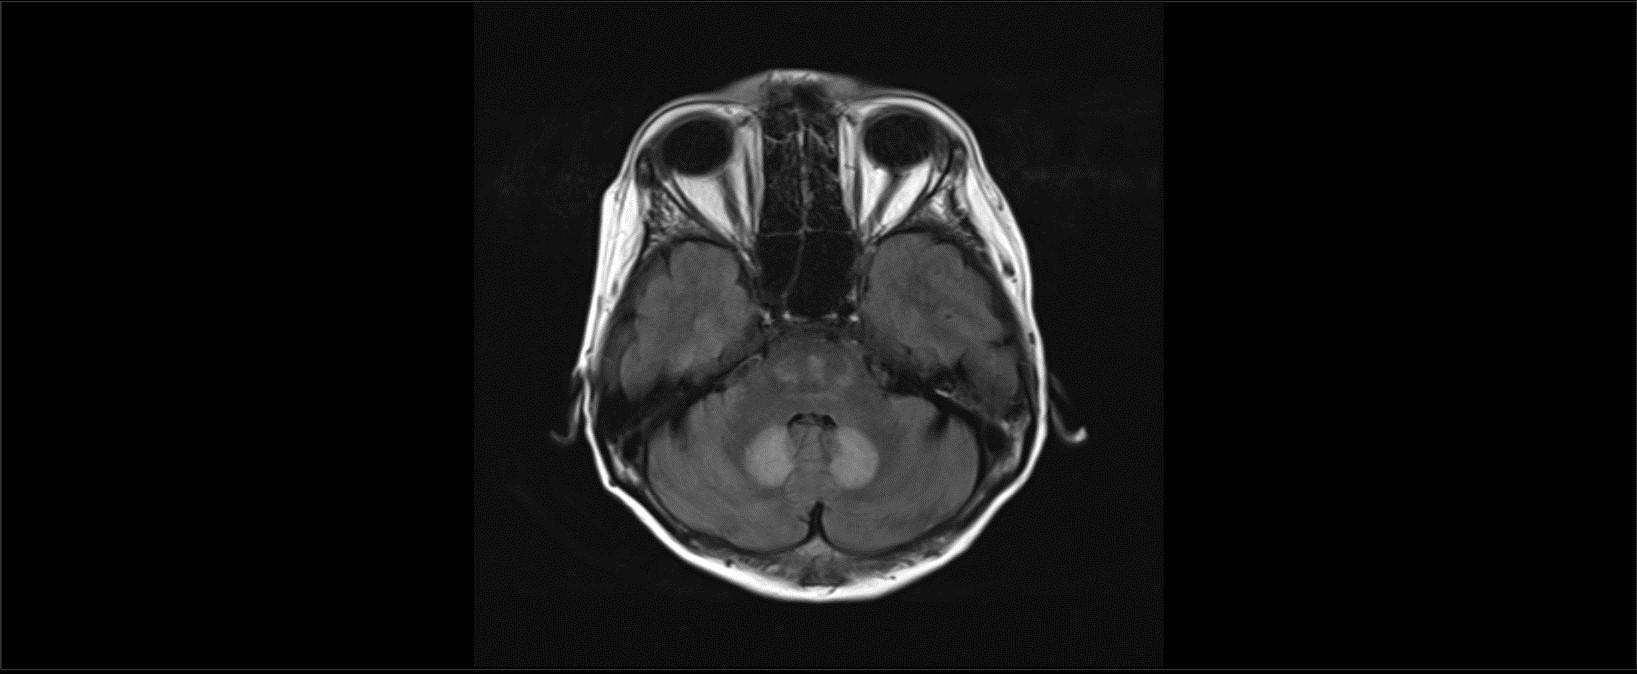

Case Presentation: We report a case of a 44 year old female with a history of hepatitis C and alcoholic cirrhosis, abstinent from alcohol for about two years, who presented from a nursing facility with few weeks of confusion and bilateral lower extremity weakness and imbalance. Her family reported that she was oriented, communicative and ambulating without assistance a week prior to admission. She was compliant with her lactulose but mentioned that her appetite had decreased since initiation of lactulose. She was started on oral metronidazole 500mg every 8 hours with the onset of her confusion and family reported worsening in her weakness and imbalance with this change mentioned above. On exam, she was weak in her bilateral hip flexors with 4/5 strength on testing. Her finger to nose testing was preserved but she was sluggish on heel to shin testing bilaterally suggesting truncal ataxia. Pertinent labs findings were as follows: sodium 134 mmol/L, creatinine 0.56 mg/dl, WBC 8200. Her UA and other infectious workup was negative. Her ammonia was minimally elevated at 44 umol/L (normal: 11-35 umol/L). MRI brain with and without contrast revealed regions of T2/FLAIR signal hyper intensity located in the dentate nuclei, splenium of corpus callosum, and in the pons. This pattern of signal abnormality, specifically involving the dentate nuclei bilaterally is typical for metronidazole-induced encephalopathy (MEI) (Image 1A). The involvement of the splenium of the corpus callosum also suggest likely component of Marchiafava-Bignami (MB), commonly seen with malnutrition due to deficiency in B vitamins (Image 2A). Metronidazole also causes reversible peripheral neuropathy worsening his patient’s unsteadiness and gait imbalance.

Discussion: MIE is a rare toxic encephalopathy with characteristic T2 hyper intense lesions of the bilateral dentate nuclei leading to predominantly cerebellar findings on exam. The mechanism of metronidazole toxicity has not been elucidated, and the apparent preferential involvement of the dentate nucleus remains puzzling. It can be differentiated from Wernicke’s encephalopathy, which presents similarly, but has MRI findings of bilateral symmetric T2 hyper intense lesions in the periventricular regions of the mammillary body, medial thalamus, floors of the third and fourth ventricles, periaqueductal gray matter, and midbrain tectum. Additionally, we cannot rule out Marchiafava-Bignami especially given involvement of the entire corpus callosum and clinical history suggesting malnutrition and alcoholism. Our patient did improve with discontinuation of metronidazole and she did report improvement in her strength at her post discharge follow up suggesting a large component of acute metronidazole encephalopathy and neuropathy